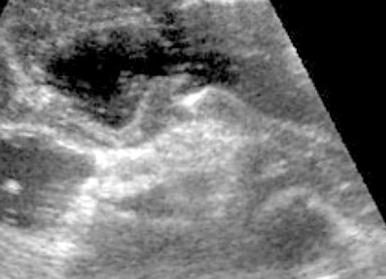

Язва желудка

Язва желудка на УЗИ

Язва – очень серьёзная патология, которая возникает на фоне стрессов, частых дуодено-гастральных рефлюксов (выброс содержимого двенадцатиперстной кишки в полость желудка), длительный приём противовоспалительных препаратов, хилекобактерной инфекции (Helicobacter pylori), характере питания (приверженность к кислой, острой, пряной пище), приём реактогенных веществ (алкоголь, уксус, иногда сода и других) и других состояниях, сопровождающихся снижением защитных и/или повышении поражающих факторов на желудок.

Серьёзность состояния выражается тем, что заболевание (язвенная болезнь желудка) может осложняться. Ультразвуковая картина язвы желудка выражается в дефекте его стенки глубже слизистого и подслизистого слоя, очаговом или множественном. Хронические язвы выглядят как дефект стенки с нависанием одного края. Прободная язва (одно из опасных осложнений) выглядит как отверстие в стенке желудка.